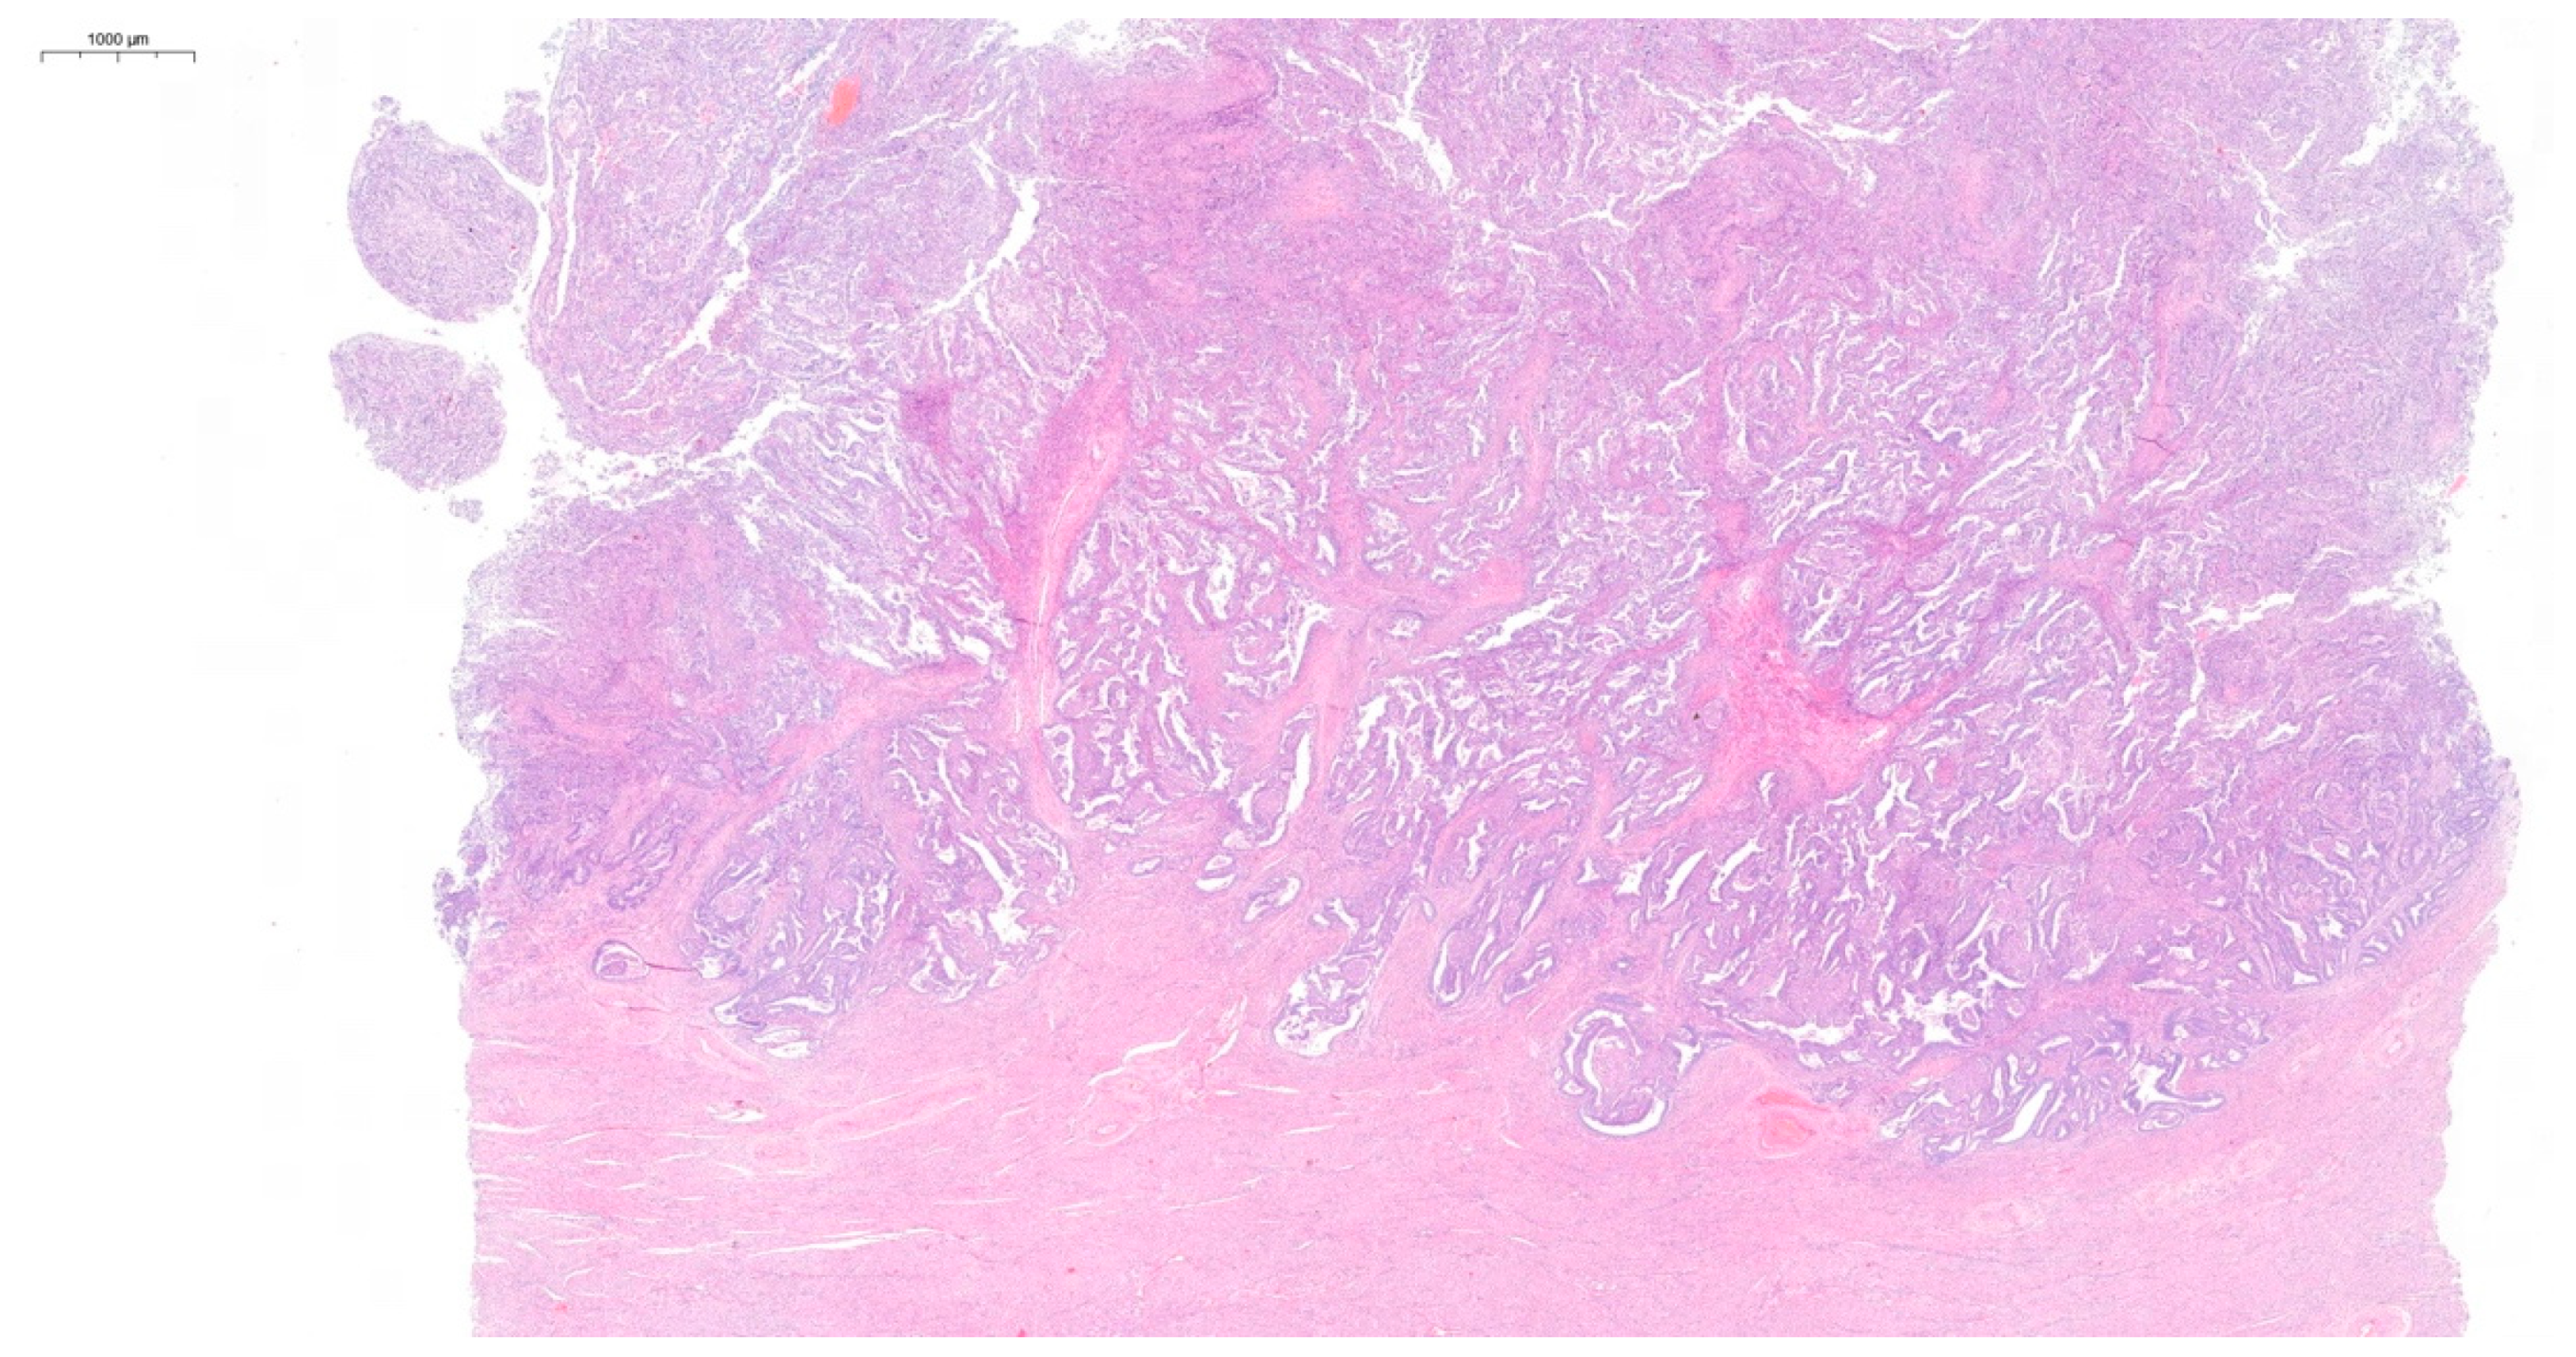

Postoperative histopathological examination revealed grade 2 (G2) endometrioid cancer of the left ovary (Figure 2). No signs of angioinvasion or invasion of the nerve trunks were found. The cancer structure penetrated the surface of the ovarian capsule. The cancer cell immunophenotype was cytokeratin 7 (CK7) (+), cytokeratin 20 (CK20) (−), estrogen receptor (ER) (+), Wilms’ tumor gene 1 (WT1) (−). The left fallopian tube was normal. Functional cysts and a corpus luteum cyst were found in the right ovary. The right fallopian tube was normal. In the body of the uterus, complex endometrial hyperplasia with atypia was observed, as well as small foci of low-grade endometrioid cancer (Figure 3). The cancer was limited to the endometrium. No signs of angioinvasion or invasion of the nerve trunks were found. Leiomyomas and adenomyosis were discovered in the body of the uterus. In the left parametrium, a microfocus of cancer structure was present. No cancer was found in the right parametrium. No metastasis was observed in the lymph nodes. No cancer was found in the omentum or in the peritoneal tissue samples. Neoplastic cells were observed in the peritoneal fluid. The histopathological findings indicated two individual cancer foci—endometrial and ovarian. The stages of the tumors were endometrial adenocarcinoma IA and ovarian adenocarcinoma IIB. The patient qualified for chemotherapy. The patient’s condition was under control for five years following the surgery. During the first two years, a follow-up appointment took place every three months, then once every six months. The patient has been free of recurrence until now.

Figure 2.

Hematoxylin and eosin (H&E) staining of the G2 endometrioid cancer of the ovary.

Figure 3.

Hematoxylin and eosin (H&E) staining of the complex endometrial hyperplasia with atypia and low-grade endometrioid cancer.